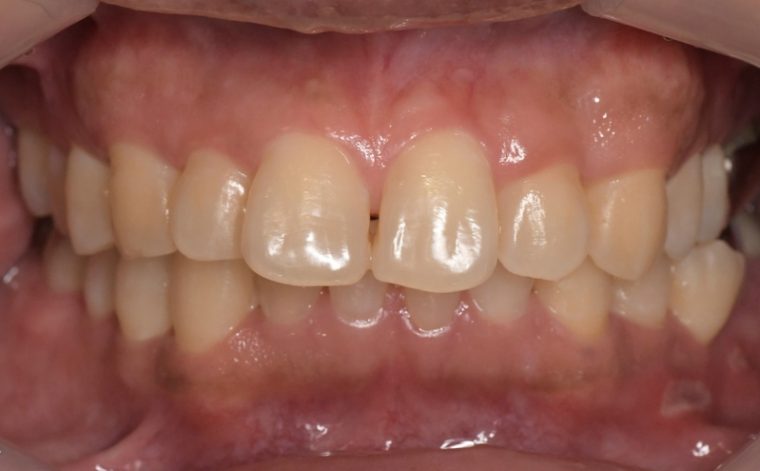

症例4

before

症例

after

抜歯前

抜歯後

基本情報

年齢・性別 26歳・男性

主訴 主訴:左下親知らず痛い

治療部位:左下8番

治療内容 ・左下8番埋伏抜歯

〈歯周病治療〉

①検査、資料取り(歯周ポケット検査、レントゲン14枚法、口腔内写真)、染めだし、歯磨き指導

②歯肉縁上の歯石除去、歯磨き指導、確認

③歯肉縁下の歯石除去(SRP)

④再評価

⑤メインテナンス

(2024年8月現在)

治療期間 約1ヶ月

治療費 合計:19,950円

〈内訳〉(全て保険診療3割負担)

①初診検査、左下8番埋伏抜歯:10,620円

②染めだし・歯磨き指導:1,110円

③歯磨き指導、確認・縁上歯石除去:2,830円

④縁下歯石除去(SRP)×2回:1,680円(×2回)

⑤再評価(歯周精密検査)・歯磨き指導:2,030円

リスク・副作用 ・歯石除去後、個人差はありますが1週間程度、歯を磨くといつもより出血することがあります。

・治療の結果、腫れていた歯ぐきが引き締まることで、歯ぐきが下がったように見えます。

下がった訳ではなく、本来の歯ぐきの位置に戻ったことによる見た目の変化です。

・歯ぐきが引き締まることにより、歯面が露出し知覚過敏の症状がでることがあります。

治療方針 左下の親知らずが痛いとのことでご来院された患者さまです。

親知らず周囲は汚れが落としきれておらず、歯ぐきが炎症を起こしている状態でした。

当日抜歯を希望されていたので、麻酔を効かせてから三次元的なレントゲン写真(CT)撮影し、抜歯を行いました。

その後、全顎的に歯石付着、歯ぐきの炎症が見られたので歯周病治療をその他の治療と並行して行っていきました。

特記事項 ・歯科受診約4年ぶり

・喫煙歴無し

・右下、左上の親知らずも抜歯済み

・コーヒー常飲

担当者所見 初診時は歯ブラシの交換時期を把握していなかった患者さまが歯ブラシを新しくしてから約1ヶ月後自分から歯ブラシを変えたことを教えてくださいました。

歯周病治療を進めていくうちに、患者さまの口腔内への意識が高まっていて治療が良い方向に進んでいきました。

歯周基本治療とセルフケアで歯ぐきの炎症や出血は初診時より大分改善されましたが、出血率を0%まで減らしていけるように今後は定期的な検診で歯ブラシの当て方や経過を患者さまと一緒に確認していこうと思います。